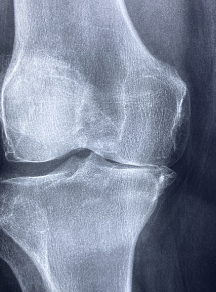

무릎 연골 손상 증상 원인 치료방법(+좋은 음식과 운동) 알아봐요. 무릎 연골은 무릎 관절의 표면을 덮고 있는 유연한 조직으로, 무릎의 움직임과 충격을 완화하는 역할을 합니다. 무릎 연골은 신체 활동, 노화 등에 의해 마모되어 손상되거나 파열될 수 있습니다. 이는 무릎 통증, 부종, 불규칙한 관절 운동 등의 증상을 일으키며, 심각한 경우 무릎 관절염으로 진행될 수도 있습니다. 무릎 연골 손상의 치료 방법에는 보존적 치료, 수술적 치료 등이 있으며, 예방적으로는 적절한 운동, 체중 관리, 안전한 스포츠 활동 등이 중요합니다. 또한, 연골이 손상된 경우 조기에 적절한 치료를 받는 것이 중요하며, 의학적 진단과 전문적인 치료가 필요합니다.